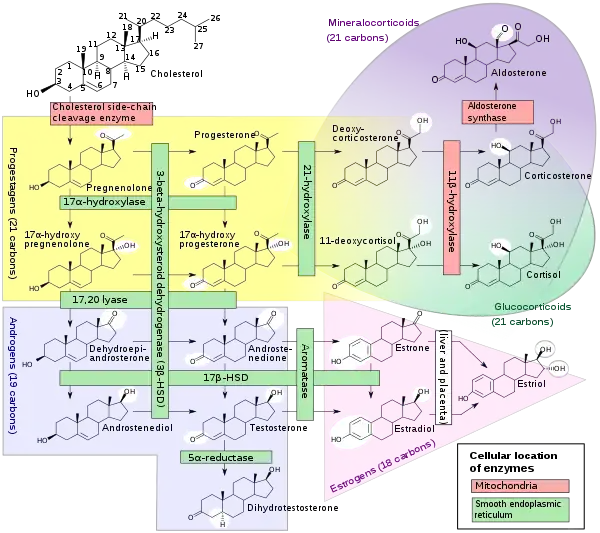

Steroid biosynthesis is an anabolic metabolic pathway that produces steroids from simple precursors. This pathway is carried out in different ways in animals than in many other organisms, making the pathway a common target for antibiotics and other anti-infective drugs. In addition, steroid metabolism in humans is the target of cholesterol-lowering drugs such as statins. It starts in the mevalonate pathway in humans, with Acetyl-CoA as building blocks, which form DMAPP and IPP. In following steps, DMAPP and IPP form lanosterol, the first steroid. Further modification belongs to the succeeding steroidogenesis. Steroidogenesis is the biological process by which steroids are generated from cholesterol and transformed into other steroids. The pathways of steroidogenesis differ between different species, but the pathways of human steroidogenesis are shown in the figure. Products of steroidogenesis include: androgens testosterone estrogens and progesterone corticoids cortisol aldosterone

Biosynthesis of testosterone Like other steroid hormones, testosterone is derived from cholesterol (see figure to the right). The first step in the biosynthesis involves the oxidative cleavage of the sidechain of cholesterol by CYP11A, a mitochondrial cytochrome P450 oxidase with the loss of six carbon atoms to give pregnenolone. In the next step, two additional carbon atoms are removed by the CYP17A enzyme in the endoplasmic reticulum to yield a variety of C19 steroids. In addition, the 3-hydroxyl group is oxidized by 3-β-HSD to produce androstenedione. In the final and rate limiting step, the C-17 keto group androstenedione is reduced by 17-β hydroxysteroid dehydrogenase to yield testosterone. The largest amounts of testosterone (>95%) are produced by the testes in men. It is also synthesized in far smaller quantities in women by the thecal cells of the ovaries, by the placenta, as well as by the zona reticularis of the adrenal cortex in both sexes. In the testes, testosterone is produced by the Leydig cells. The male generative glands also contain Sertoli cells which require testosterone for spermatogenesis. Like most hormones, testosterone is supplied to target tissues in the blood where much of it is transported bound to a specific plasma protein, sex hormone binding globulin (SHBG)[2].

Biosynthesis of cortisol

Cortisol is synthesized from cholesterol. Synthesis takes place in the zona fasciculata of the adrenal cortex. (The name cortisol is derived from cortex.) While the adrenal cortex also produces aldosterone (in the zona glomerulosa) and some sex hormones (in the zona reticularis), cortisol is its main secretion. The medulla of the adrenal gland lies under the cortex, mainly secreting the catecholamines adrenaline (epinephrine) and noradrenaline (norepinephrine) under sympathetic stimulation. The synthesis of cortisol in the adrenal gland is stimulated by the anterior lobe of the pituitary gland with adrenocorticotropic hormone (ACTH); ACTH production is in turn stimulated by corticotropin-releasing hormone (CRH), which is released by the hypothalamus. ACTH increases the concentration of cholesterol in the inner mitochondrial membrane, via regulation of the STAR (steroidogenic acute regulatory) protein. It also stimulates the main rate-limiting step in cortisol synthesis, in which cholesterol is converted to pregnenolone and catalyzed by Cytochrome P450SCC (side chain cleavage enzyme).